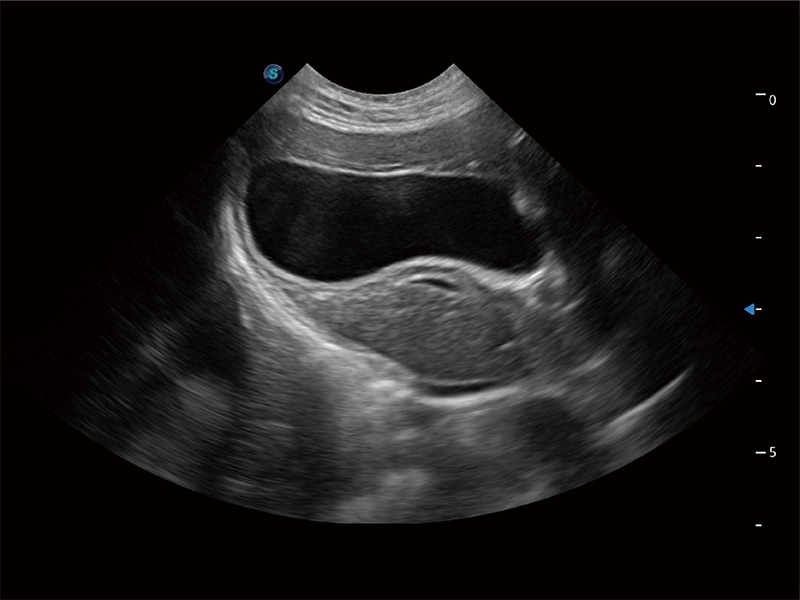

优异的基础图像

ProPet 80 全新的动物超声智能软件和丰富的探头群,为动物医生提供了高清晰度和精细分辨率的图像,无论在宠物、马科、畜牧还是实验室动物等应用中都可以轻松应对,为您的日常工作带来满意的体验。

(猫)胆囊

(犬)胎儿四腔心

(猫)二尖瓣M型